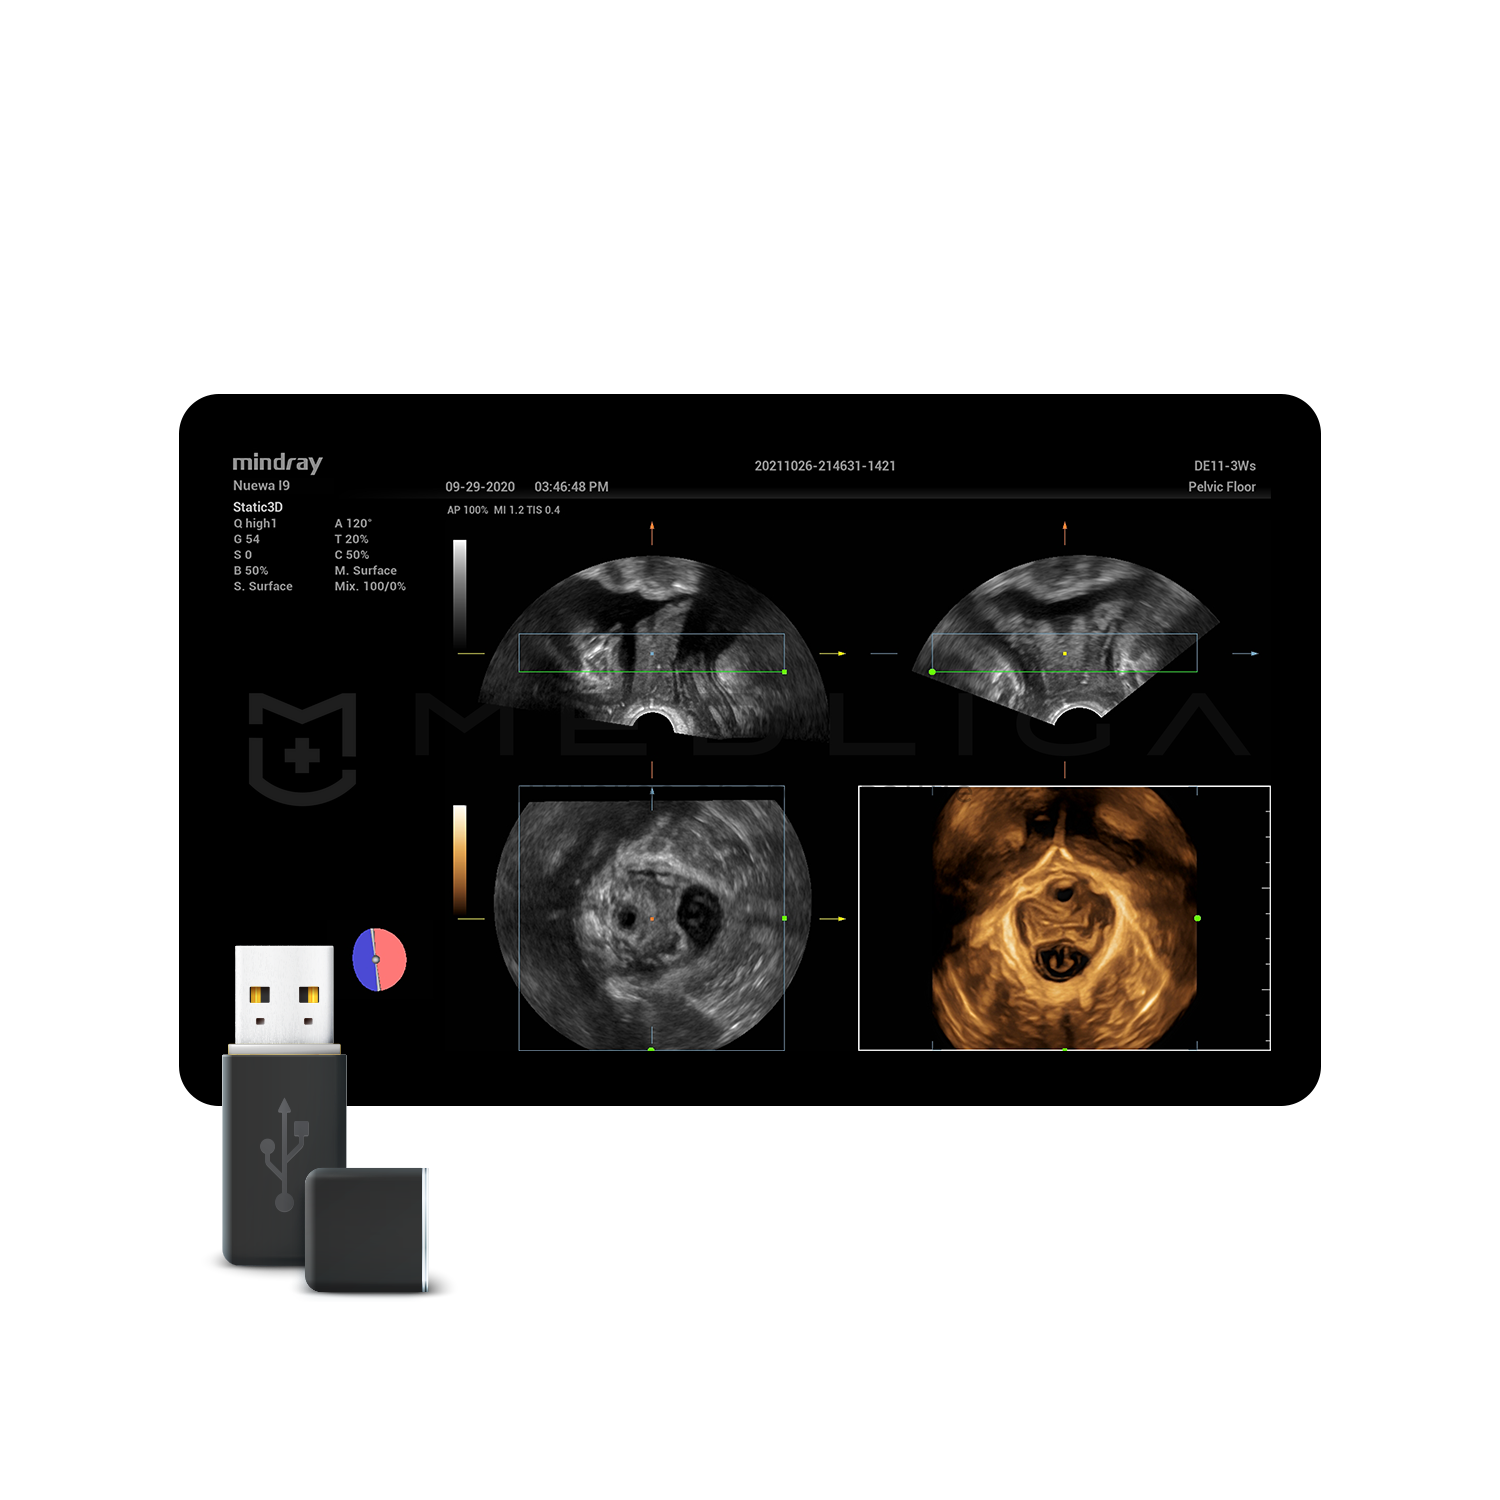

Программное обеспечение для автоматических измерений параметров и оценки функции мышц тазового дна.

Smart Pelvic - новое решение, позволяющее значительно упростить диагностическую процедуру и свести к минимуму время исследования функций мышц тазового дна. Благодаря чрезвычайно простому пользовательскому интерфейсу, программа генерирует стандартную систему координат и автоматически просчитывает все связанные измерения в течение нескольких секунд.